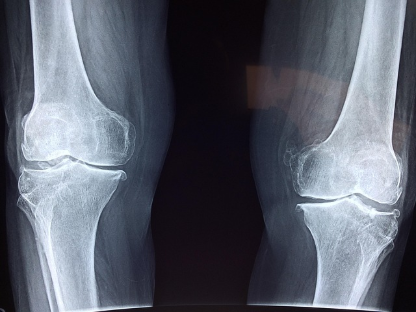

관절은 뼈와 뼈가 만나 움직이는 부위로, 연골, 활액막, 인대, 근육 등이 정밀하게 맞물려 움직임을 조율합니다. 하지만 나이가 들수록 연골은 점차 닳고, 활액의 윤활 기능도 저하되며, 염증성 물질이 증가하면서 통증과 뻣뻣함을 호소하는 사람이 많아집니다. 특히 무릎, 고관절, 손목 등 자주 사용하는 관절은 반복적인 사용과 체중 부담으로 마모가 빠르게 진행됩니다. 과거에는 관절 통증이 단순한 노화의 결과로 여겨졌지만, 최근에는 식습관, 운동량, 체중, 호르몬 변화, 유전 등 다양한 요인이 작용하는 복합적인 퇴행성 질환으로 보고 있으며, **초기부터 적극적인 관리와 기능성 보충이 권장**됩니다. 관절 건강을 위해 가장 핵심이 되는 것은 **연골 보호와 염증 완화**이며, 이를 위한 과학적인 기능성 성분이 이미 다양한 연구를 통해 입증되고 있습니다. 글루코사민, 콘드로이틴, MSM, 보스웰리아, UC-Ⅱ 등은 관절 관련 건강기능식품의 대표 성분으로 자리잡았고, 현재도 계속 진화 중입니다. 본 글에서는 이들 주요 성분의 특징, 작용 기전, 병용 여부, 제품 선택 팁과 복용 시 주의사항을 전문가의 시선으로 정리해드립니다.